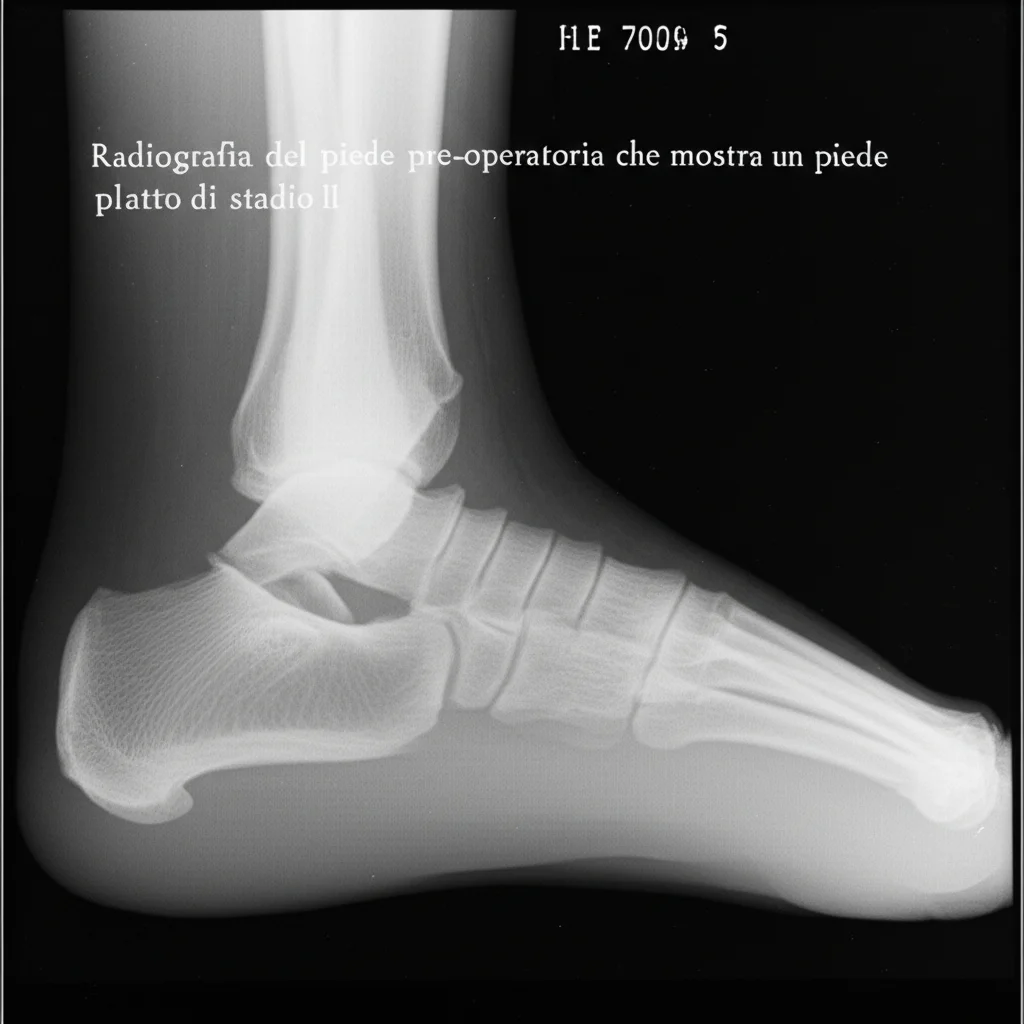

Ciao a tutti! Oggi voglio parlarvi di un argomento che tocca da vicino molti adulti: il piede piatto acquisito (AAF). Non parliamo di quel leggero appiattimento che magari ci portiamo dietro dall’infanzia, ma di una condizione che può svilupparsi in età adulta, portando con sé dolore, difficoltà a camminare e una serie di fastidi. In particolare, mi concentrerò sullo stadio II, quello in cui il piede è ancora flessibile ma inizia a dare problemi seri, come l’incapacità di sollevarsi sulla punta di un solo piede.

Lo studio ha seguito per due anni 114 pazienti (per un totale di 149 piedi), di cui 92 trattati con osteotomia di Hintermann e 57 con osteotomia di Evans. I ricercatori hanno analizzato un sacco di parametri: misure radiografiche pre e post-intervento (come l’angolo di Meary, la copertura talo-navicolare, l’angolo dell’arco mediale, ecc.), punteggi clinici per valutare dolore, funzionalità e qualità della vita (AOFAS, SF-36, Pain-NRS, UCLA) e, cosa fondamentale, i segni di degenerazione articolare a distanza di tempo.